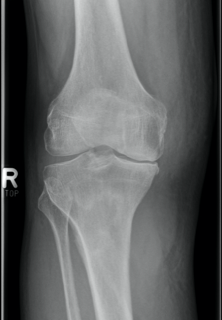

Um welche Modalitäten handelt es sich?

- Röntgen p.a. und lateral, CT coronar Knochenfenster, CT axial Weichgewebsfenster

Was fällt in der Projektionsradiographie auf?

- Verdichtung im Recessus suprapatellaris

- Aufhellungslinie in Projektion auf die Femurkondylen

- Erhöhter tibialer Slope

- Hypertransparenz tibial

- Subluxationsstellung im Kniegelenk